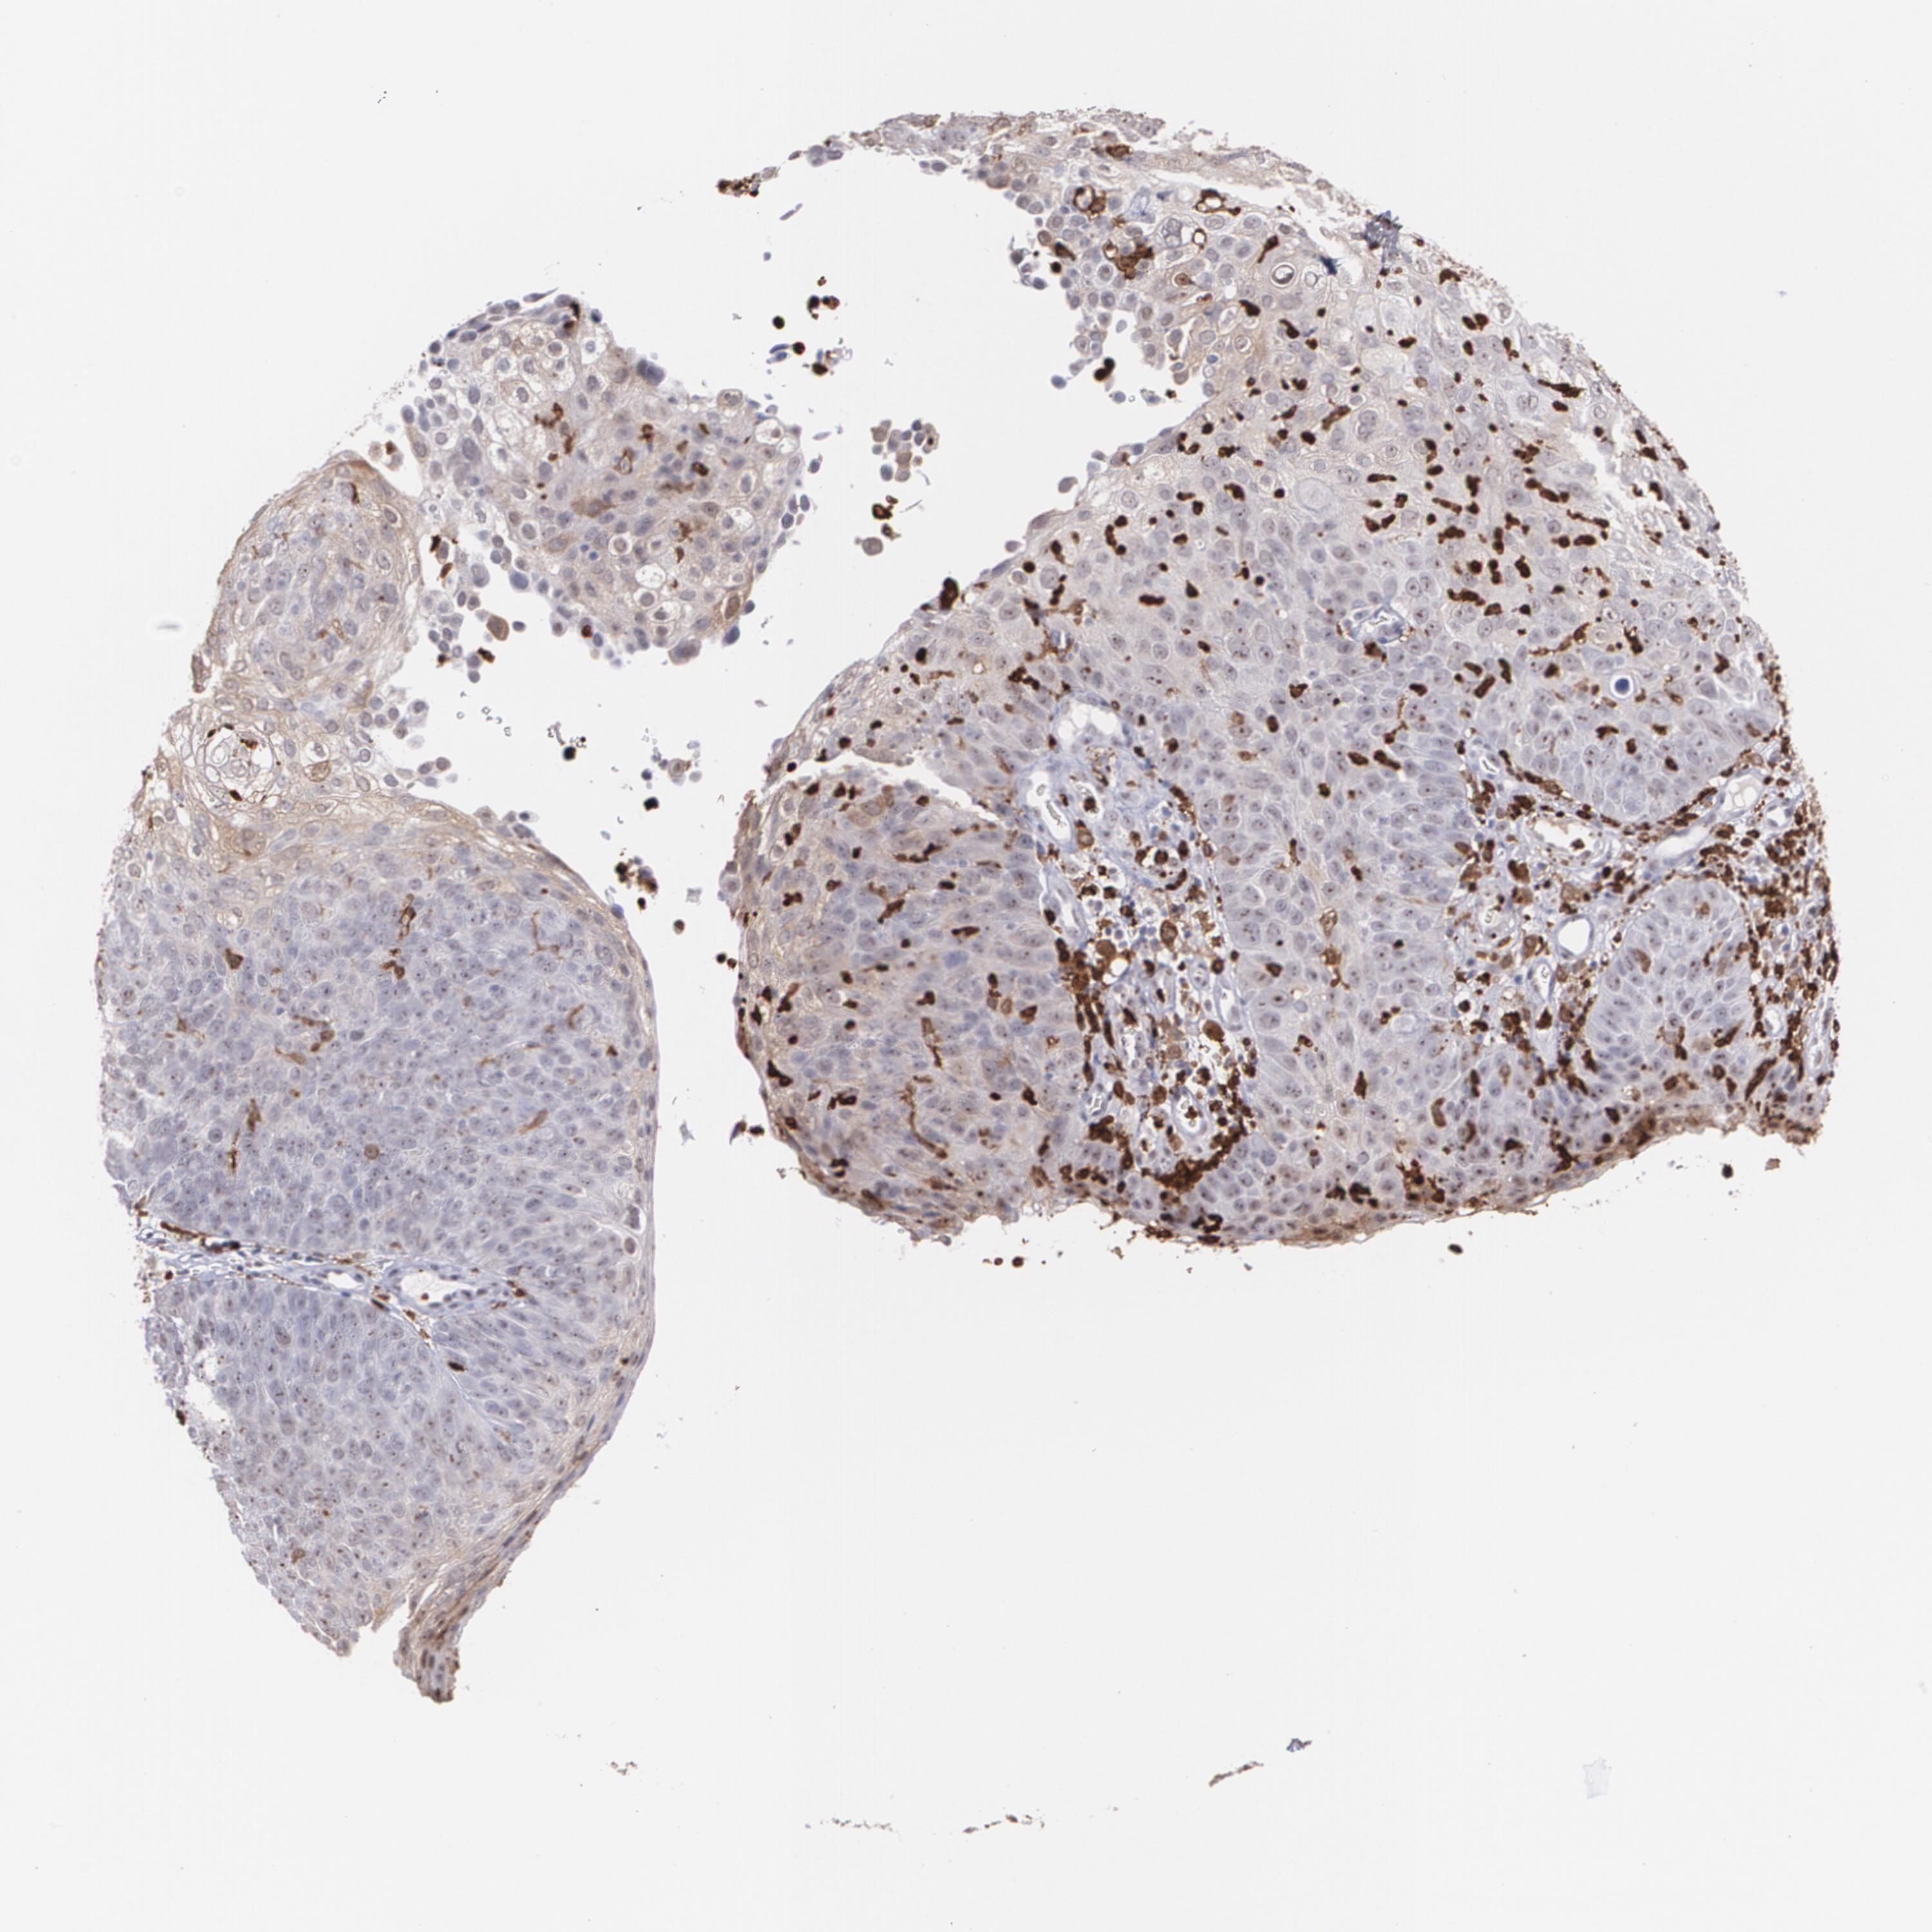

SKIN CANCER - Protein expressioni

A mouse-over function shows sample information and annotation data. Click on an image to view it in a full screen mode. Samples can be filtered based on level of antibody staining by selecting one or several of the following categories: high, medium, low and not detected. The assay and annotation is described here.

Each image is clickable and will lead to virtual microscopy that enables deeper exploration of all samples and also displays staining intensity scores, fraction scores and subcellular localization as well as patient and tissue information for each sample.

Antibody HPA002327

Staining

High

Medium

Low

Not detected

Intensity

Strong

Moderate

Weak

Negative

Quantity

>75%

75%-25%

<25%

None

Location

Nuclear

Cytoplasmic/membranous

Cytoplasmic/membranous,nuclear

Squamous cell carcinoma, NOS

Basal cell carcinoma